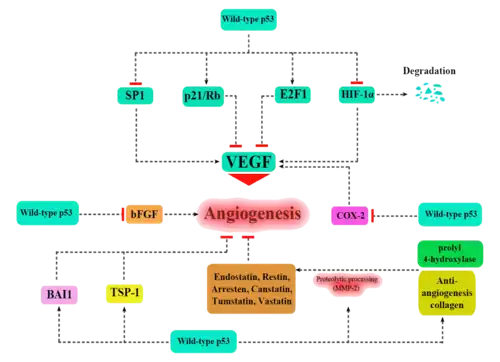

Apart from the cellular and molecular effects above, p53 has a tissue-level anticancer effect that works by inhibiting angiogenesis.[52] As tumors grow they need to recruit new blood vessels to supply them, and p53 inhibits that by (i) interfering with regulators of tumor hypoxia that also affect angiogenesis, such as HIF1 and HIF2, (ii) inhibiting the production of angiogenic promoting factors, and (iii) directly increasing the production of angiogenesis inhibitors, such as arresten.[53][54]